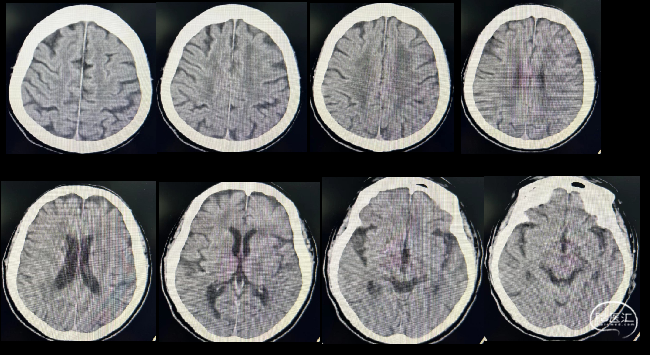

21:05 评估头部CT,排除出血后,转运10米旁核磁检查室完善脑梗死核磁一站式检查,期间完成急诊采血。

21:10 DWI+MRA序列:MRI显示左侧半卵圆中心、基底节区呈高信号,MRA显示左侧颈内动脉闭塞。

绿道核磁脑梗死一站式检查:MRI显示左侧半卵圆中心、基底节区呈高信号,MRA显示左侧颈内动脉闭塞。

术后次日复查头部CT,NIHSS评分下降至5分。

术后第七日NIHSS评分下降至2分。